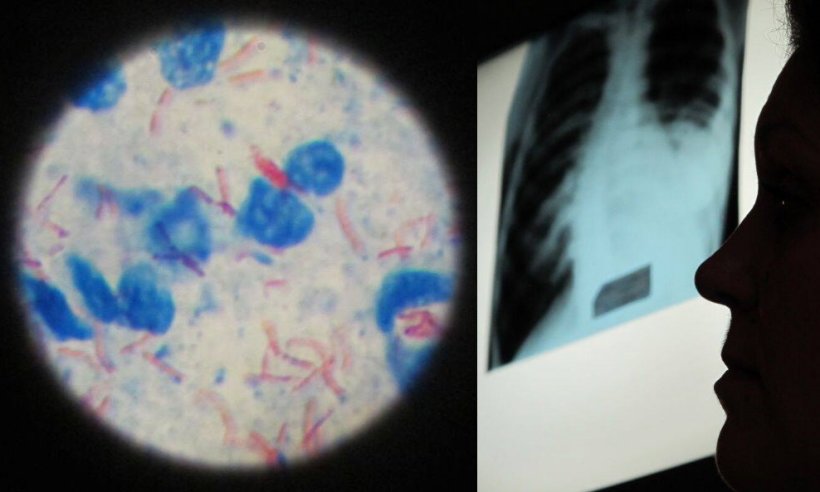

Eine aktuelle Studie mit Förderung des Deutschen Zentrums für Infektionsforschung (DZIF) warnt vor dem Beginn einer Epidemie der extensiv resistenten Tuberkulose (XDR-TB) in Europa, die Ärzte ohne wirksame Medikamente zur Behandlung von Tuberkulose zurücklassen könnte.

Durchgeführt in der Republik Moldau, einem der Länder mit der weltweit höchsten Belastung durch resistente Tuberkulose, liefert die im Fachjournal Clinical Microbiology and Infection veröffentlichte Arbeit erstmals landesweite Belege in der nördlichen Hemisphäre für das Auftreten von Resistenzen gegen die Medikamente der WHO-Gruppe A – das Rückgrat der heutigen Tuberkulosebehandlung.

Die Analyse von mehr als 1.000 Patienten, die zwischen 2021 und 2022 behandelt wurden, ergab, dass bei 40% derer, bei denen die Therapie fehlschlug, die Tuberkulosebakterien neue Resistenzen entwickelten. Unter diesen Fällen waren die Raten alarmierend hoch: 75% der Patienten mit Therapieversagen trugen Fluorchinolon-resistente Stämme, 40% zeigten eine Resistenz gegen Bedaquilin, und 38% waren resistent gegenüber Linezolid. Zuvor war eine Resistenz gegen Bedaquilin, das wichtigste Medikament in der Behandlung der resistenten Tuberkulose, vor allem in Südafrika dokumentiert worden.

Die moldauischen Daten zeigen nun, dass das landesweite Auftreten von Resistenzen gegen WHO-Gruppe-A-Medikamente auch in Europa stattfindet und die Befürchtung einer unkontrollierten Ausbreitung weckt. „Diese Ergebnisse sind ein Weckruf“, sagt Studienleiter Dr. Dumitru Chesov von der Staatlichen Universität für Medizin- und Pharmazie in Chișinău, Republik Moldau, der gleichzeitig als Wissenschaftler am Forschungszentrum Borstel, Leibniz-Lungenzentrum, in Deutschland arbeitet. „Die Resistenz nimmt gerade gegen die Medikamente zu, die das Rückgrat der Behandlungsregime für Patienten mit resistenter Tuberkulose bilden. Ohne dringende Maßnahmen könnte XDR-TB in der WHO-Region Europa zu einer verheerenden Epidemie werden.“